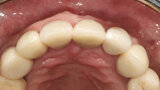

Fig. 29: The definitive restoration exhibited excellent retention of the soft-tissue profile.

Fig. 30a: The occlusal view revealed the volume maintained with

the soft-tissue cervical contours (a), and the lateral retracted view revealed an excellent soft-tissue emergence profile (b).